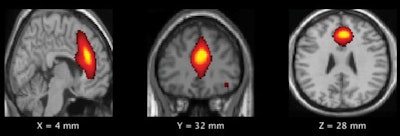

MR images of the frontal default mode network show brain regions where there was a significant difference in gray-matter volume between the high- and low-impact groups. Images courtesy of Murugesan et al and RSNA.This is the third year in a row that Murugesan and UT colleagues have presented results correlating brain changes with playing football. At RSNA 2017, they showed how MRI brain scans acquired before and after the start of the football season revealed abnormalities in young players' default mode network after only one season of play. And two years ago, current study co-author Elizabeth Moody Davenport, PhD, discussed how they saw changes in both structural and functional imaging after one season.

Their theory proved accurate, as the frontal default mode network demonstrated a significant increase in spectral power in the high-impact group (p = 0.00018), compared with results from the low-impact players. There was also a statistically significant increase in gray-matter volume in the same frontal regions of the default mode network for the high-impact group (p = 0.005).